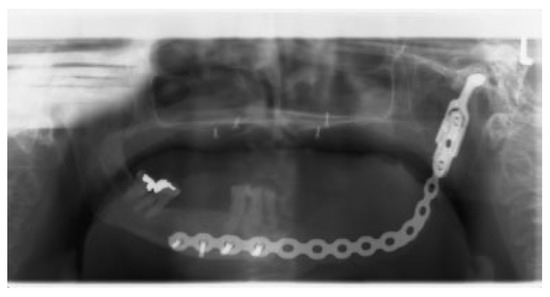

In 15 patients, 14 ablative surgical interventions were recorded, with 14 receiving primary or secondary reconstructive procedures; in one patient, no reconstructive procedure was performed due to a compounding medical condition (Table 2). This patient was excluded from further analysis due to lack of reconstruction. Eight patients had primary head and neck cancer, but in only four patients the condyle was involved due to infiltration, while four suffered from ORN. One patient suffered from a rare benign tenosynovial giant cell tumor. Two patients suffered from extensive osteomyelitis, and bisphosphonate osteonecrosis afflicted two patients. One patient had to be operated on twice due to hypertrophic bone formation around the metal condylar head and represents the only major complication in our series. She suffered facial nerve damage during the second surgery in a postradiated field, with the facial nerve lying on the reconstruction plate used in the first surgery (Figure 1). Six of the fourteen reconstruction surgeries took place in a radiated field, explaining the two plate exposures in an unrelated area, away from the condylar reconstruction. Two patients received total joint reconstructions combined with one and in the other two free flaps. Five patients received fibula flaps alone and one received a vascularized costochondral graft, while all of the others had metal condylar prostheses with or without a free flap (Figure 2, Figure 3 and Figure 4). Follow-up ranged from 2 to 84 months with an average of 30 months. In total, five patients suffered from complications that could be considered acceptable, as they all could be corrected with minor revision surgery or occlusal adjustment. One patient suffered from facial nerve damage after a reconstruction plate in which metal condyle had to be removed in a radiate. In 11 patients, reliable information was obtained regarding mouth opening of which 9 showed a marked improvement of more than 5 mm. Three patients had a decrease in mouth opening, but all could be regarded as functional as no mouth opening of less than 30 mm was recorded (Figure 4).

Figure 2.

Osteoradionecrosis of the right mandible.